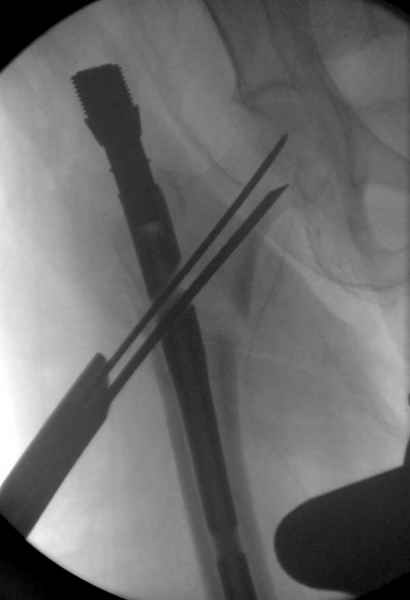

Здесь сканнированные снимки импланта и операционные снимки больной.

На этом снимке процесс компрессии нижним болтом.

Итог